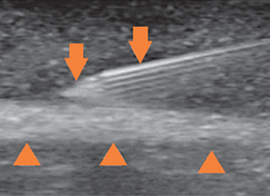

초음파 유도 주사치료

• 초음파로 주사 바늘을 확인하며 정확하고 안전하게 치료 부위에 약물을 주입할 수 있습니다.